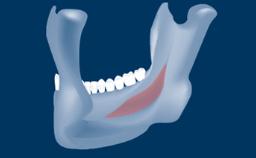

In this short microlearning module on digitally guided sinus floor elevation, we delve into a specialized aspect of the digital workflow for implant-guided surgery, focusing on the use of digital guides in the sinus floor elevation technique.

• describe the indications for digital guides in SFE